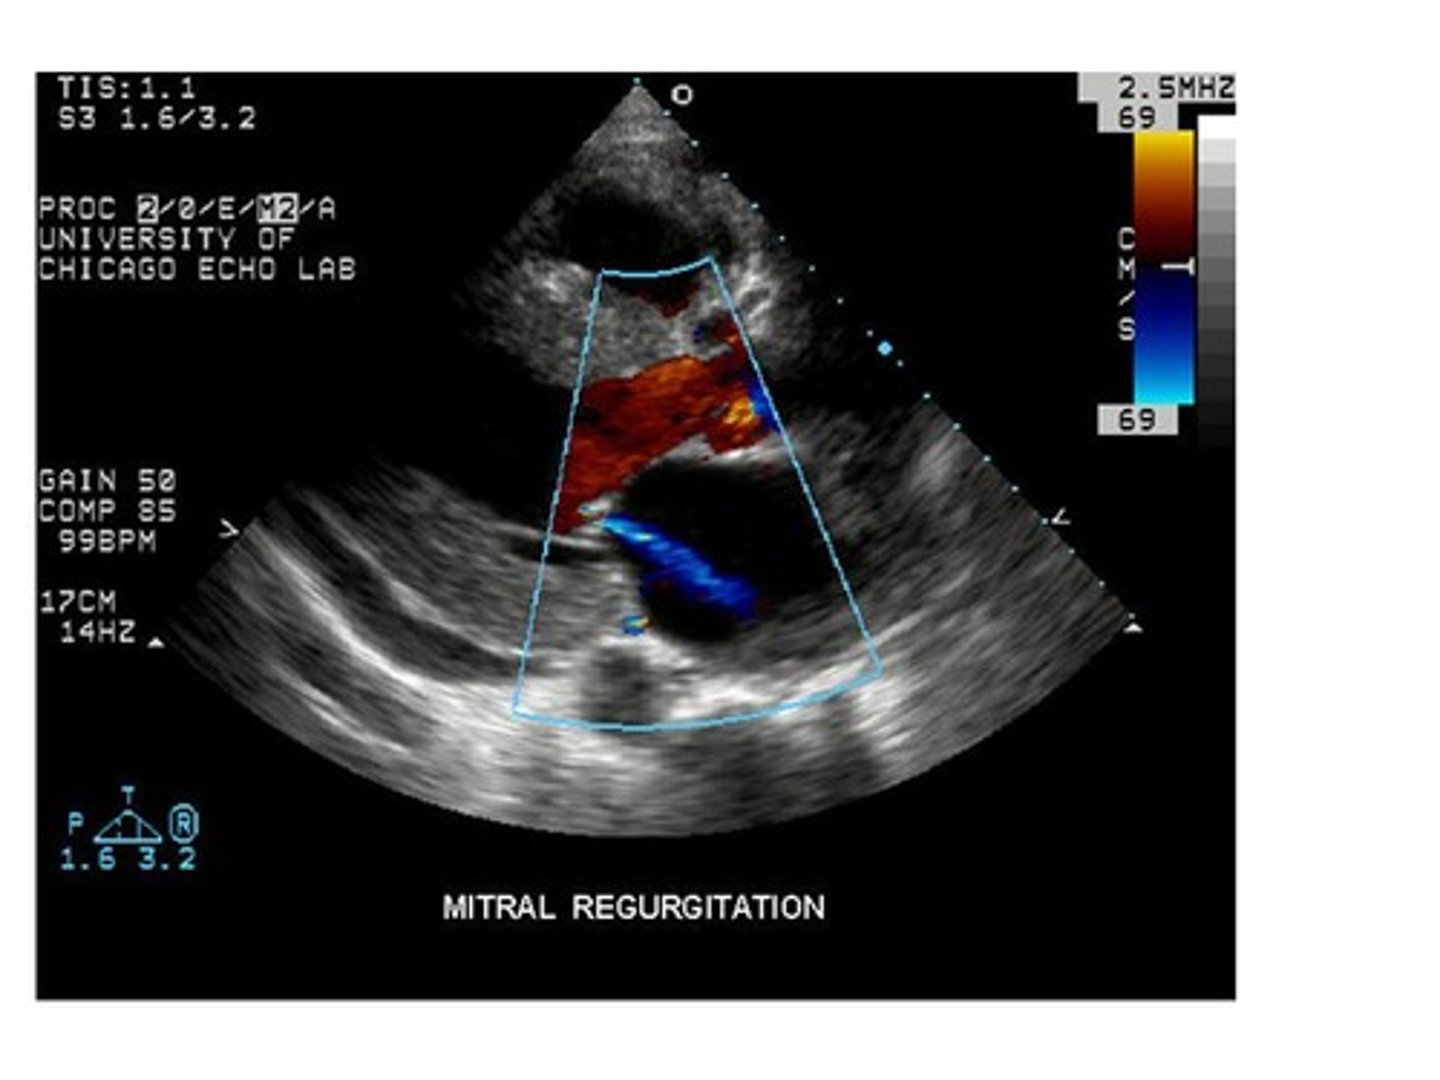

When blood leaks back into the chamber it came from, it is known as:

reflux

stenosis

regurgitation

spontaneous